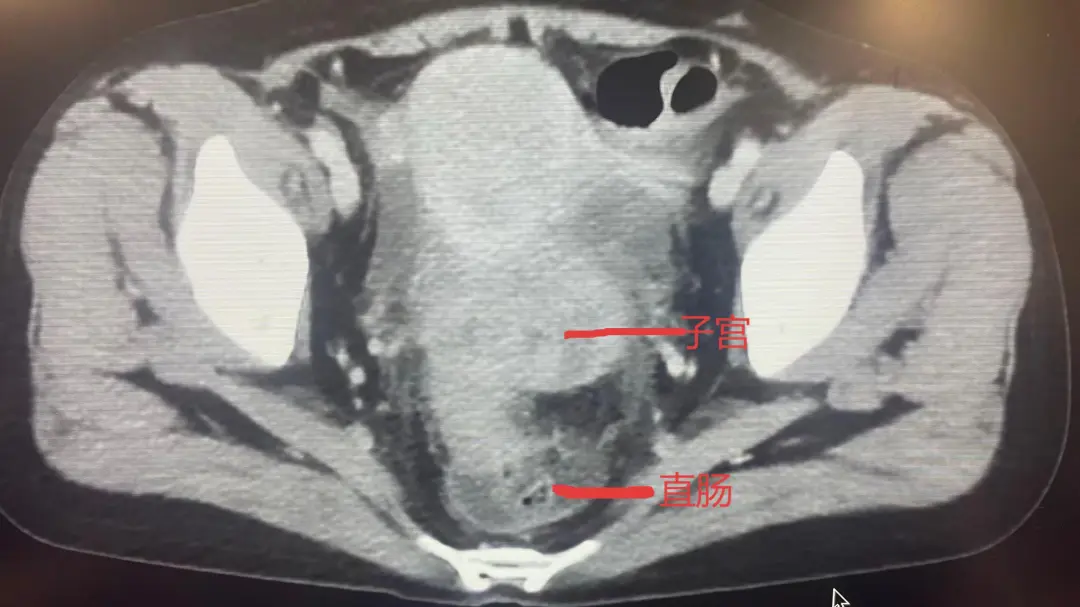

患者弓女士此前确诊直肠恶性肿瘤,进一步检查发现肿瘤已侵犯子宫及小肠,于医院肿瘤科行化疗+靶向治疗,但内科治疗出现耐药,患者持续便血,导致贫血难以纠正,不仅生活质量差,更时刻危及生命。肿瘤科郝淑兰主任及陈海富医师启动MDT,在医务科组织下,肿瘤科、普外科、妇科、麻醉科共同讨论病情,最终制定实施全麻下腹腔镜直肠肿瘤切除术+部分小肠切除术+子宫及附件切除术的联合手术方案。